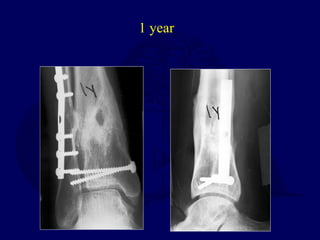

1986 - 24 yo Male

1 year

14 years

 Works light labor

 Prefers high top boots

 Occasional pain

 Ankle score 80